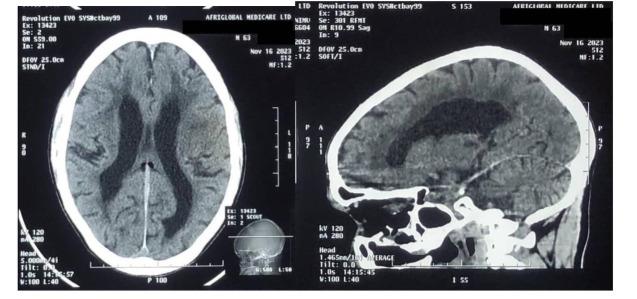

A Case of Lacunar Stroke in a Patient with Possible Normal Pressure Hydrocephalus (NPH).

The patient's symptoms, including insidious gait difficulties, speech impairment, and memory loss, led to a suspected diagnosis of NPH. However, the sudden improvement of neurological deficits indicated a vascular cause. Computed Tomography (CT) imaging identified supporting evidence of a lacunar stroke, leading to a revised diagnosis.

患者的症状,包括隐匿性步态困难、言语障碍和记忆力丧失,导致怀疑诊断为NPH。然而,神经功能缺损的突然改善表明为血管性病因。计算机断层扫描(CT)成像确定了腔隙性卒中的支持证据,从而导致诊断修正。